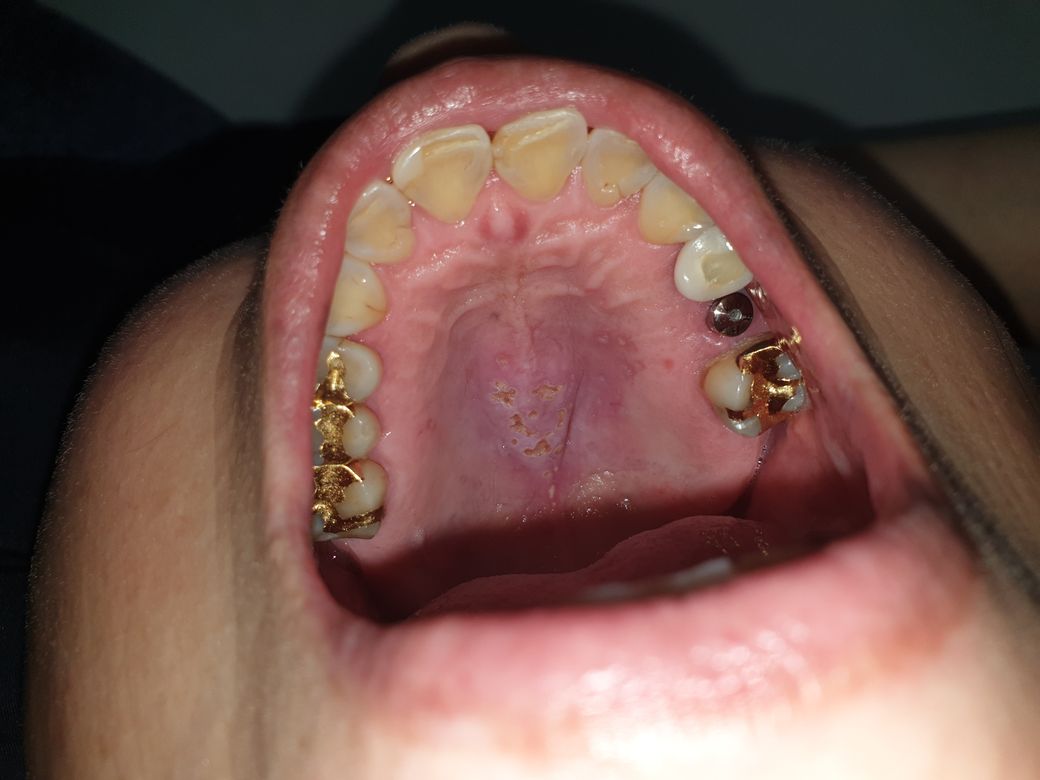

입 천장에 염증 같은 게 생겼는데 뭔지 알 수 있을까요?

어머니께서 갑자기 입 천장이 좀 튀어나온 거 같다고 하셔서 자세히 보니

첨부된 사진 처럼 염증? 살이 패여있더라고요.

여쭤보니 2~3일 전 죽 끓이면서 입 천장을 데였는데 그 이후로 제대로 못쉬어서 이러는 게 아닐까 하시는데

혹시 무슨 증상인지 알 수 있을까요?

구내염 같이 큰 문제 없는 거라면 알보칠 바르고 잘 쉬면 나을까요?

데인 후 구내염이 생겼을 가능성이 있어보입니다.

면역력이 약해진 경우 점막세포가 손상되었을 때 세균의 침입이 용이하게 되어 구내염이 더 잘 발생할 수 있습니다.

충분한 휴식과 스트레스 관리, 비타민과 무기질을 포함한 균형잡힌 식단, 금연, 금주, 구강 청결관리를 해주는 것이 도움이 되겠습니다.